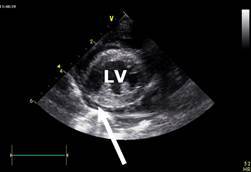

D/d:

Could lead to atrial rupture and pericardial effusion - acute (poor prognosis)